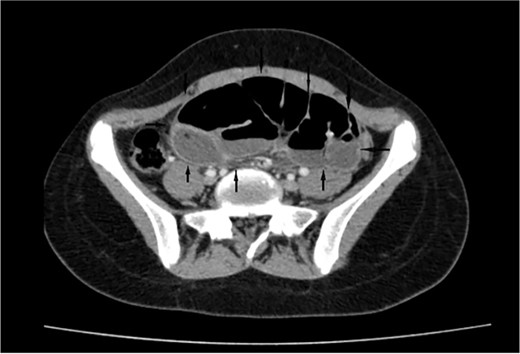

On a retrospective review of our patient’s ECT, we recognised a membrane encapsulating the small intestine centrally, which indicates the diagnosis of ACS (Figs 4 and 5).

Retrospective review of ECT (axial section), a membrane encapsulates the small intestine centrally indicates the diagnosis of ACS (black arrows).